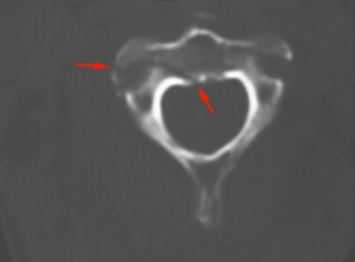

КТ является методом выбора для оценки костного повреждения. Однако более полную информацию о состоянии спинного мозга даёт МРТ.

КТ. Перелом тела С2 (красные стрелки).

Особую категорию составляют пациенты, у которых, несмотря на наличие неврологической симптоматики, не выявляется изменений при рентгенографии или КТ. Число таких пациентов составляет около 10%. Среди различных механизмов подобных травм наиболее вероятна кратковременная компрессия спинного мозга задней продольной связкой и дисками, либо, жёлтой связкой и пластиной дуги. Посколько резкие сгибания и разгибания наблюдаются при высокой подвижности в сегментах, такие травмы более вероятны в шейном отделе позвоночника. Спондилолиз усугубляет эту ситуацию, приводя к центральному синдрому спинного мозга. В этих случаях необходимой является МРТ позвоночника. Характерными находками, которые мы часто видим при травмах при МРТ в СПб, являются отёк спинного мозга и гематома, причём последняя при МРТ позвоночника плохим прогностическим фактором в отношении восстановления неврологического дефицита. К наиболее тяжелым осложнениям шейной травмы относится расслоение магистральных артерий, определяемое по МРТ, МРА или КТ и КТА. В высоком поле такой вид травм лучше виден чем в открытом МРТ. МРТ СПб позволяет выбирать место МРТ, однако, острая травма шейного отдела позвоночника требует высокоспециализированного нейрохирургического отделения